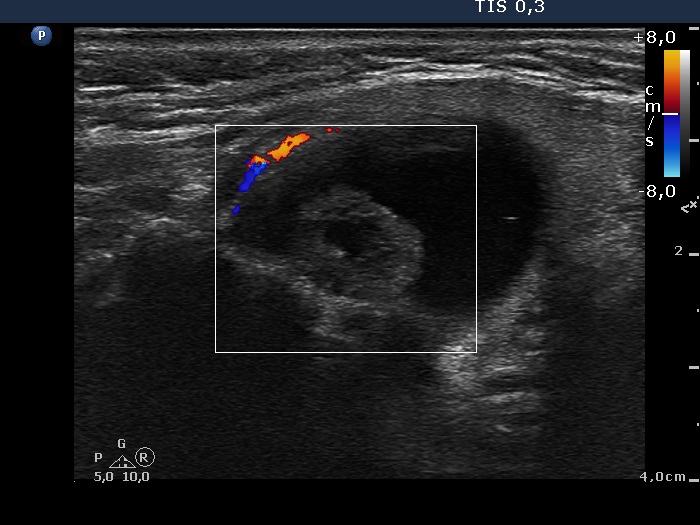

Ultrasonography. The thyroid was echonormal. There was large cyst in the right lobe. The cyst seemed to be a peripheral-type lesion with an inhomogeneous solid part having numerous hyperechogenic figures which belonged to the non-specific category. There were two hyperechogenic lesions in the right while a moderately hypoechogenic one in the left lobe.

After aspirating 9 mL troubled fluid it became evident that the cyst indeed is a central-type lesion.